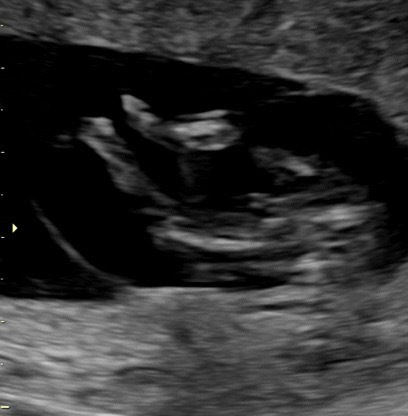

๋ค๋ฆฌ์ฌ์ด ๐ถ๏ธ์ผ๊น์ ํฏ์ค์ผ๊น์

๋ค๋ฆฌ ์ฌ์ด๊ฐ ์ฐํ๋๋ฐ ๋ชฐ๊น์ฉ???